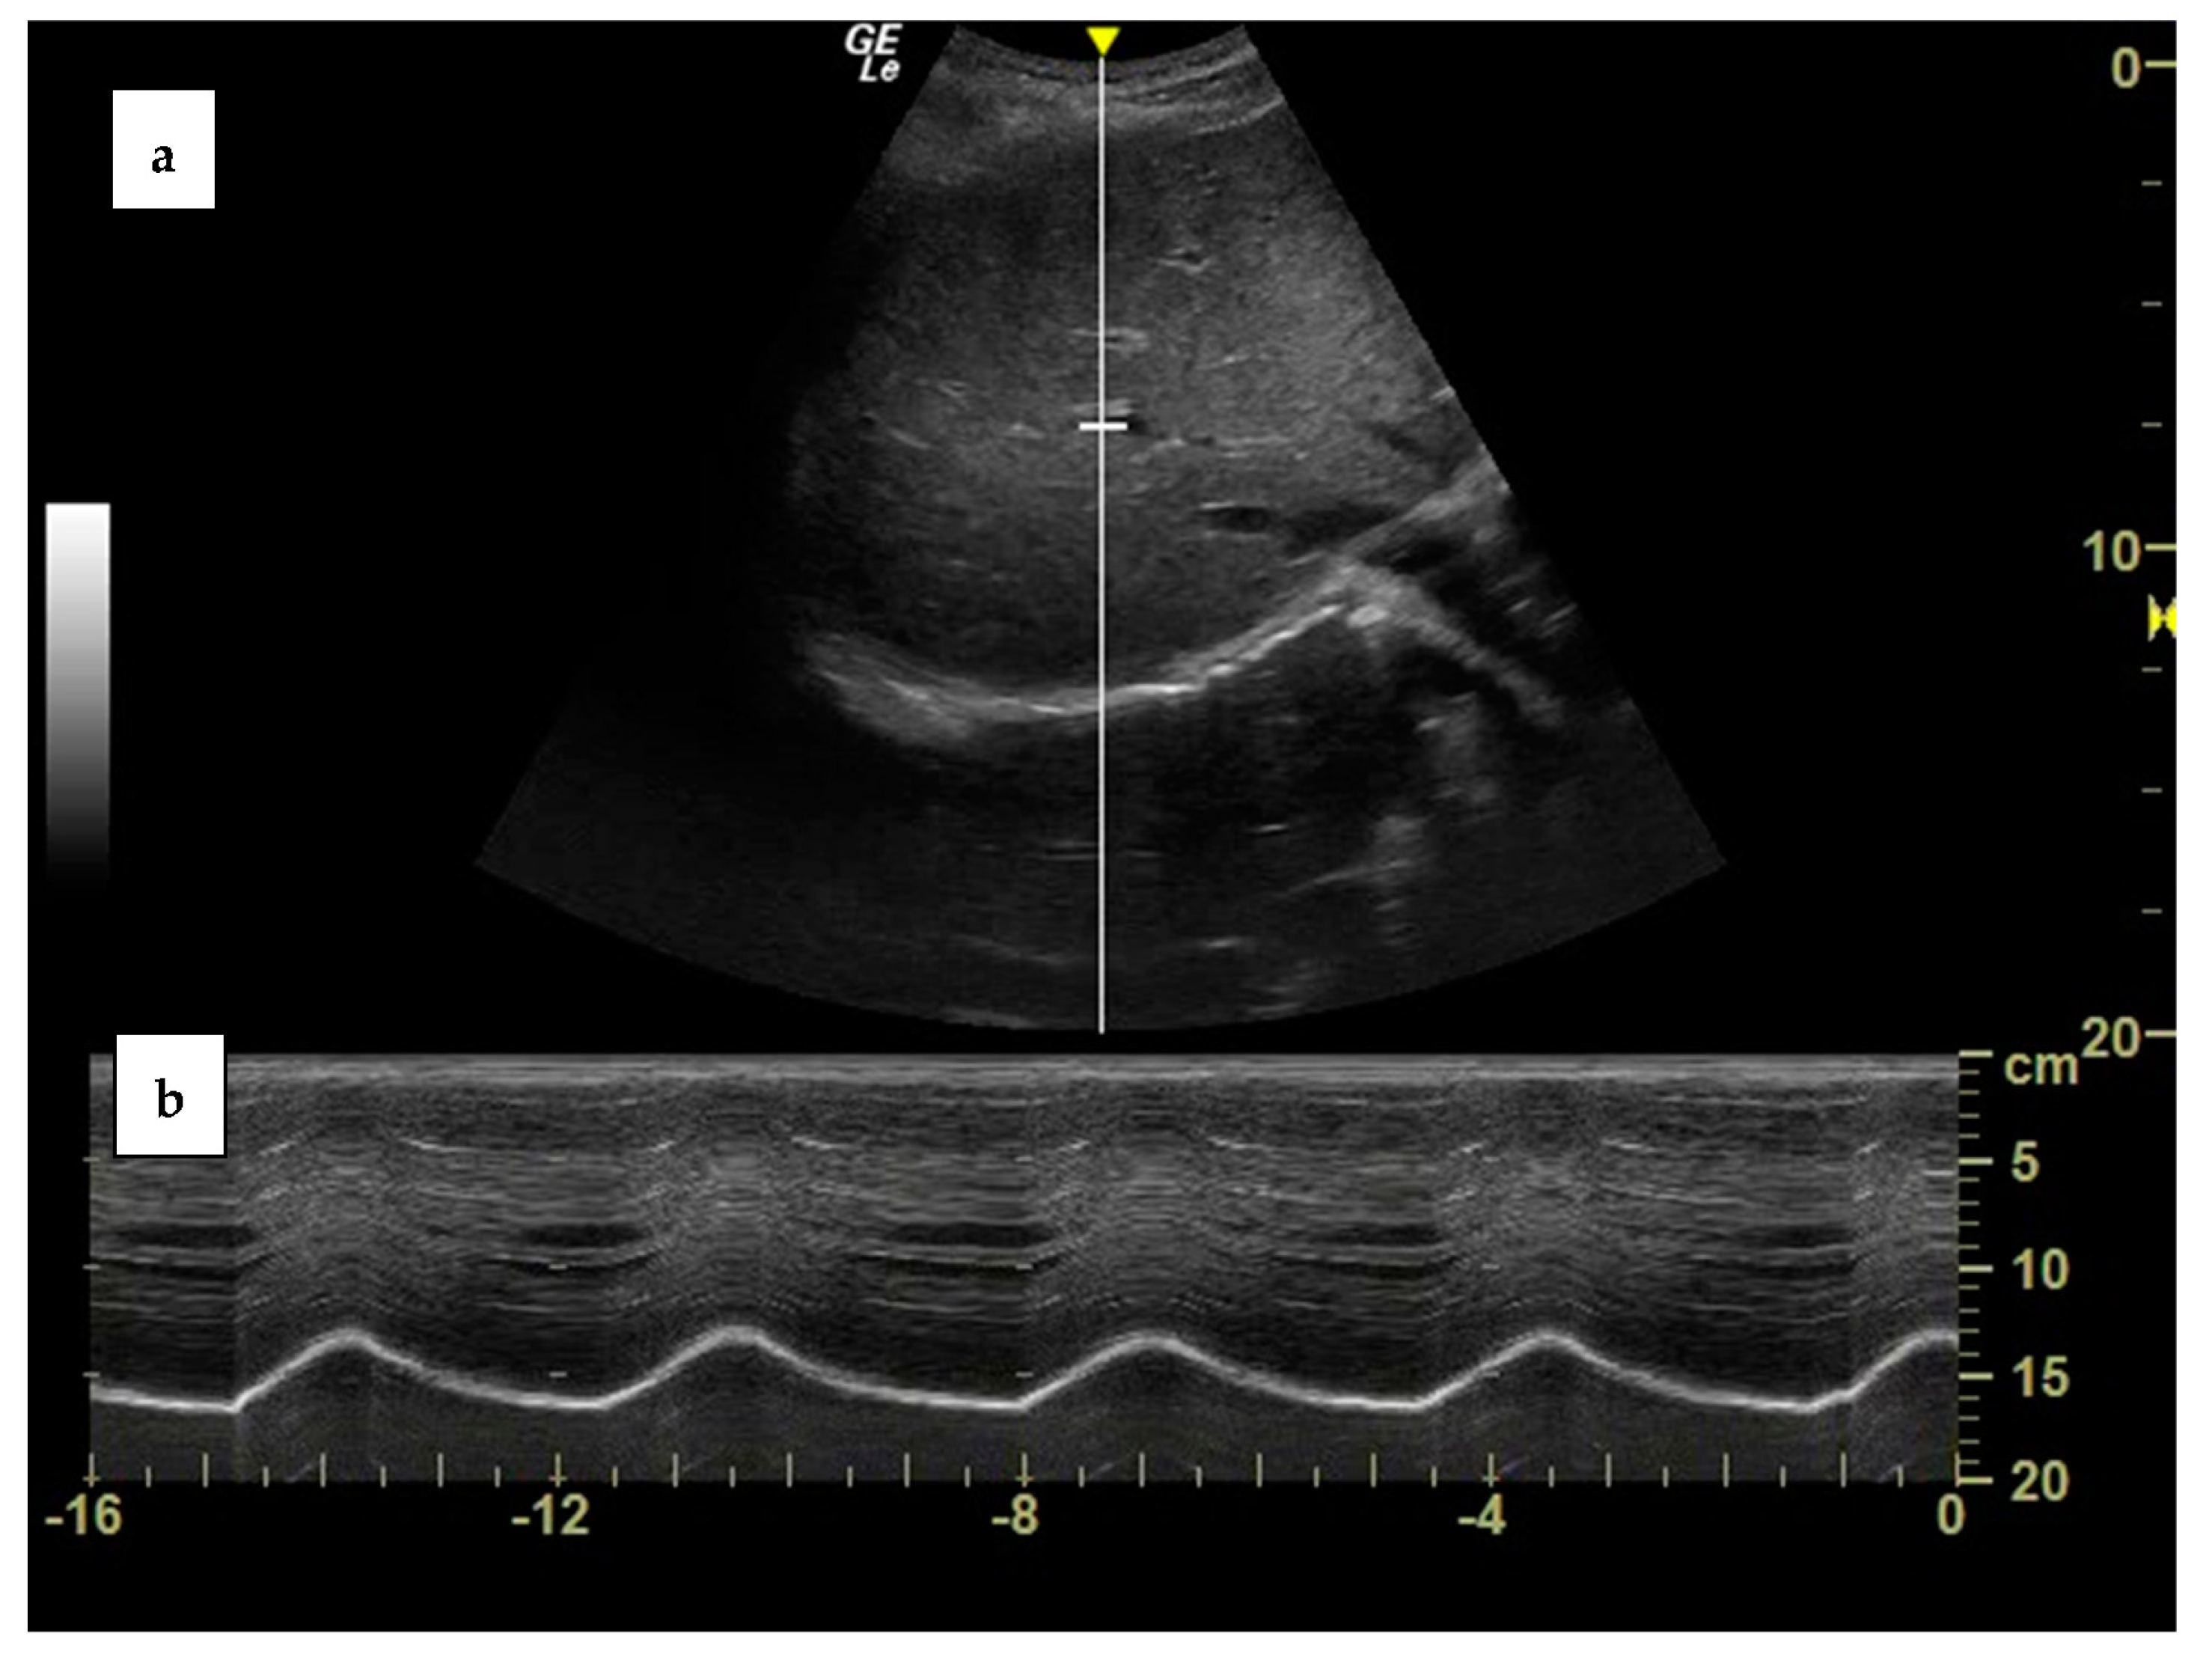

Ultrasonography also allows the measurement of the diaphragmatic cranio–caudal excursion during the respiratory cycle. This requires employing curvilinear, low-frequency probes (2–6 MHz), which can be positioned just below the right costal arch, on the right midclavicular line, and directed upwards and laterally, so that the liver acts as an acoustic window and the ultrasound beam reaches the dome of the diaphragm perpendicularly. The diaphragm will be visualized as a bright, hyperechogenic line which lays over the profile of the liver. After having obtained a good visualization of the diaphragm in 2D brightness (B) mode, ultrasonography will be switched to movement (M) mode, in order to visualize the diaphragmatic respiratory excursions over time [41] (Figure 2). The same procedure can also be executed by pointing the probe towards the left midclavicular line, thus using the spleen as an acoustic window, or on the right or left mid axillary line, even if visualization of the diaphragm is often suboptimal [9]. The maximum diaphragmatic excursion can be measured as the difference between the position of the diaphragm at functional residual capacity (FRC) and total lung capacity (TLC), while tidal excursion is the difference between the positional FRC and the end-inspiratory position during resting breathing. Ultrasonography assessment of the diaphragmatic excursion has been proven to have a good inter- and intra-observer reproducibility (Table 1) [24,26].

Figure 2.

Visualization of the diaphragmatic dome from the right subcostal view in brightness (B) mode (a) and of the diaphragmatic excursion in motion (M) mode (b) in a healthy subject. Own image.